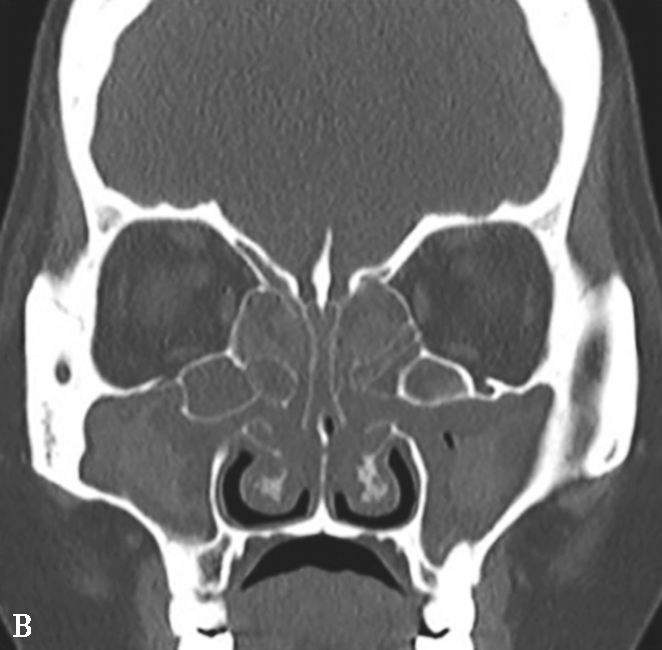

图1-3-20 慢性鼻窦炎

A~C.横断面、冠状面及矢状面CT平扫,示右侧额窦、上颌窦黏膜增厚,窦腔内可见软组织密度影,窦口鼻道复合体狭窄,右侧上颌窦窦壁骨质增生硬化、肥厚;D~F.同一患者横断面MR T 2 WI、T 1 WI及横断面增强T 1 WI,示右侧上颌窦黏膜增厚,呈T 1 WI等信号、T 2 WI高信号影,增强扫描示右侧上颌窦黏膜线样强化